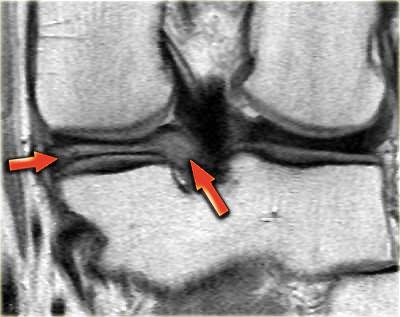

Như bạn đã đoán được qua tiêu đề của đoạn này, đây là một trường hợp sụn chêm lật (flipped meniscus).

Sụn chêm lật là một dạng đặc biệt của rách dạng quai xô (bucket-handle tear).

Sụn chêm lật xảy ra khi mảnh vỡ của sừng sau bị lật ra phía trước, khiến sừng trước của sụn chêm có vẻ to hơn bình thường.

Bên trái là một trường hợp sụn chêm lật khác.

Lần này ở phía trong (medial).

Một phần sừng trước bị lật ra phía sau.

Chỉ một phần nhỏ của sừng trước được nhìn thấy ở phía trước.

Hầu hết các trường hợp sụn chêm lật xảy ra ở phía ngoài (lateral).

Dây chằng chéo trước (ACL) ngăn mảnh sụn chêm di chuyển hoàn toàn vào hố gian lồi cầu.

Trên hình ảnh mặt phẳng coronal, trước tiên sẽ thấy sừng trước to và phồng lên.

Ở phía sau sẽ thấy sừng sau rất nhỏ.